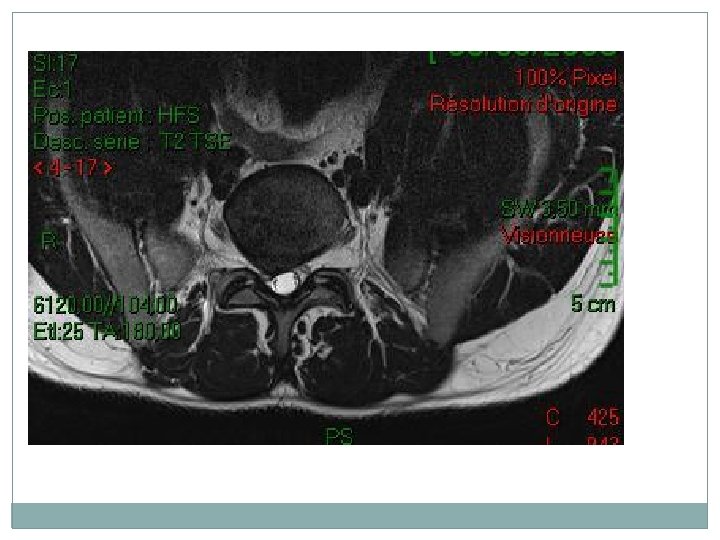

imagerie � 2 La tomodensitométrie (TDM) du rachis lombo sacré: permet de préciser l’HERNIE DISCALE son siège, de son volume, sa migration, son environnement osseux.